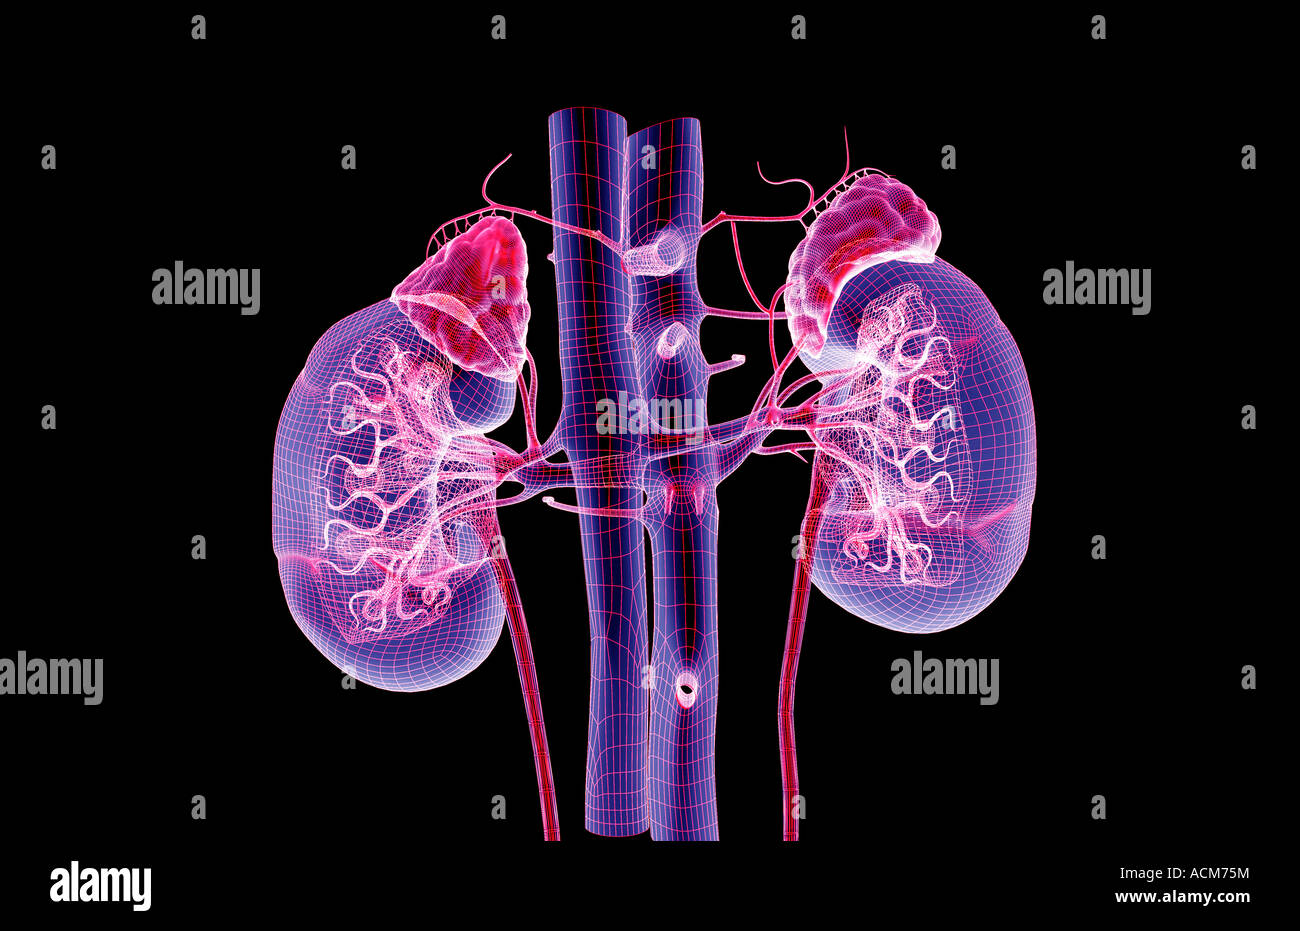

RFGMTM2D–Gehirn-System und Blut Gefäßversorgung. Grafik zeigt das Gehirn mit Arterien (rot) und Venen (blau).

RFGMTM21–Gehirn-System und Blut Gefäßversorgung. Grafik zeigt das Gehirn mit den richtigen Großhirn entfernt und Arterien (rot) und Venen (blau).